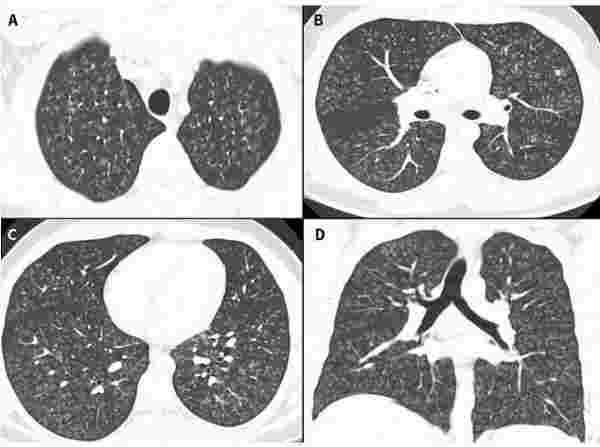

同年,多家海內外媒體報道過一名17歲加拿大少年的病例。該少年出現劇烈咳嗽,被診斷為閉塞性細支氣管炎,繼而惡化為雙肺衰竭,必須進行雙肺移植。影像學檢查顯示,其肺部“就像爆米花一樣,面目全非”。

圖2 17歲少年住院第一天的肺部影像學結果。/Canadian Medical Association Journal